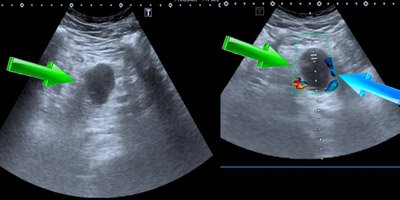

Se realiza ecografía abdominal doppler donde se visualiza una lesión hipoecogénica ovalada adyacente a la cabeza del páncreas compatible con aneurisma de la VMS. Ver Figura nº1: Ecografía abdominal (al final del artículo).

Figura 1: Ecografía abdominal

Ecografía abdominal: La flecha verde señala la lesión anecoica que corresponde a dilatación aneurismática de la vena mesentérica superior (VMS) sin señal doppler en su interior. La flecha azul señala la única zona permeable de la vena.